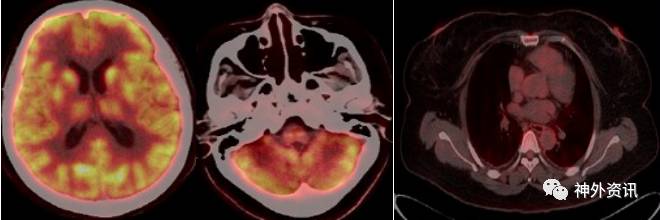

全身PET/CT显像示:①双侧额叶、顶叶、颞叶、枕叶,双侧基底节、丘脑、小脑放射性分布对称,未见明显放射性摄取增高或减低灶。②双侧胸腔少量积液;③脂肪肝;回盲部肠壁代谢稍高,提示炎症;④左肾小结石;子宫内节育环;右侧附件区囊性病变考虑(图3)。

图3. PET/CT:颅内未见明显放射性摄取增高或减低灶,回盲部肠壁代谢稍高,提示炎症,左肾小结石,右侧附件区囊性病变考虑。